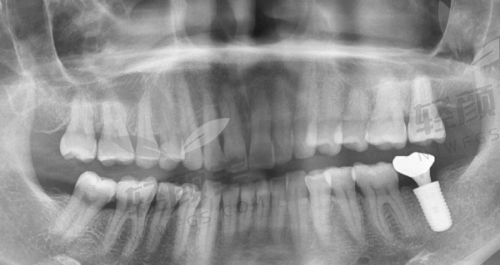

黎强医生真的特别亲切,他详细地询问了我的牙齿情况和病史,然后带我去做了全方面的口腔检查。检查设备都特别精良,整个过程也特别舒服。检查完之后,黎强医生给我分析了我的牙齿状况,耐心地给我讲解了穿颧穿翼种植牙的原理和过程。他说我的牙槽骨条件不太好,普通种植牙可能成效不佳,而穿颧穿翼种植牙可以利用颧骨和翼板的骨质,为种植体提供更稳定的支撑。我听了之后,心里踏实了不少。

黎强医生根据我的检查结果,为我制定了个性化的穿颧穿翼种植牙方案。他给我看了特别多类似实例的前后对比照片,让我对手术成效有了更直观的认识。我对方案特别满意,但是心里还是有点担心手术的风险和疼痛。黎强医生看出了我的顾虑,他安慰我说,穿颧穿翼种植牙技术已经特别成熟了,他做过特别多这样的手术,成功几率非常高。而且手术过程中会使用精良的麻醉技术,不会让我感觉到疼痛。听了他的话,我心里的石头终于落了地。